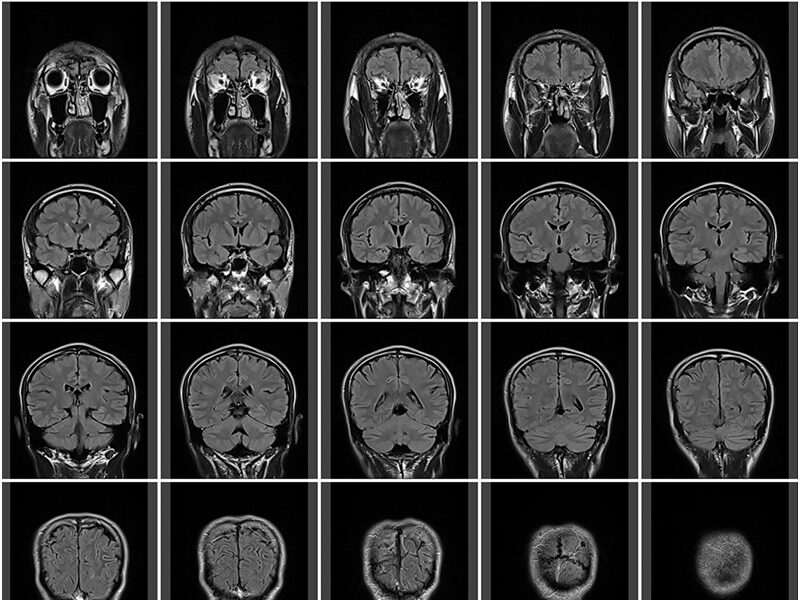

頭部CT検査

頭部CT・MRI検査

脳梗塞や脳出血など、脳の異常が疑われる場合に行います。